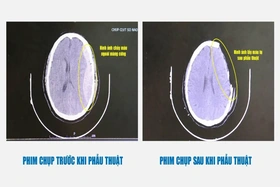

baophutho.vn Người bệnh Dương Việt Hùng (45 tuổi) trú tại huyện Sông Lô, Vĩnh Phúc nhập viện tại Bệnh viện Đa khoa tỉnh Phú Thọ trong tình trạng hôn mê.

baophutho.vn Rạng sáng 24/10/2024, Bệnh viện Đa khoa tỉnh đã tiến hành ca phẫu thuật lấy tạng của người hiến sau khi...